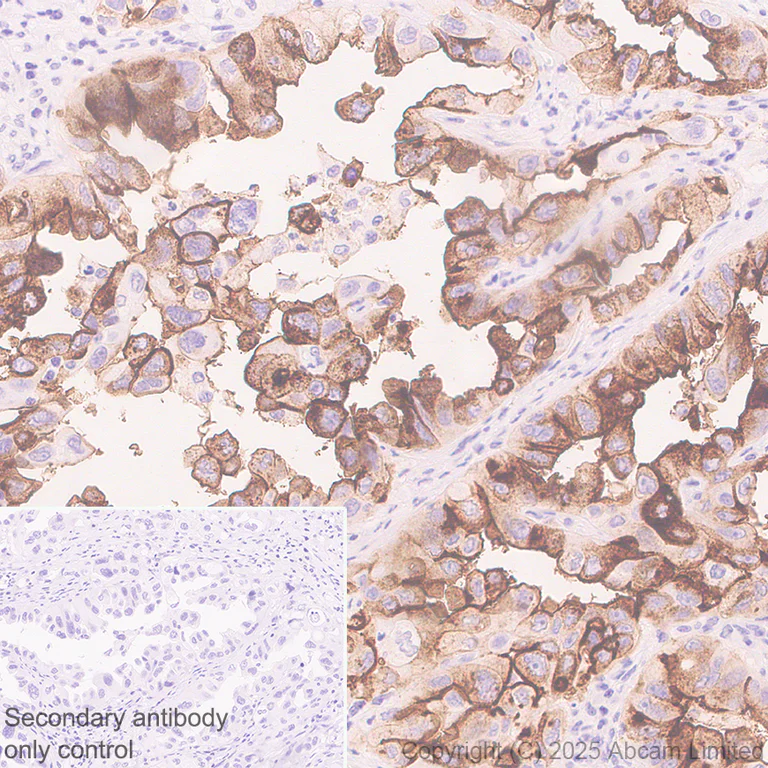

Immunohistochemistry (Formalin/PFA-fixed paraffin-embedded sections) - Anti-SLC34A2 antibody [EPR30528-645] (AB325747)

Immunohistochemical analysis of paraffin-embedded Human lung carcinoma tissue labeling SLC34A2 with ab325747 at 1/500 (0.99 ug/ml) dilution, followed by a ready to use LeicaDS9800 (Bond™ Polymer Refine Detection).

Positive staining on human lung carcinoma. The primary antibody was incubated for 30 mins at room temperature.

The immunostaining was performed on a Leica Biosystems BOND® RX instrument

Counterstained with Hematoxylin.

Secondary antibody only control : Secondary antibody is a ready to use LeicaDS9800 (Bond™ Polymer Refine Detection).

Heat mediated antigen retrieval was performed with Tris-EDTA buffer (pH 9.0, Epitope Retrieval Solution2) for 20 mins